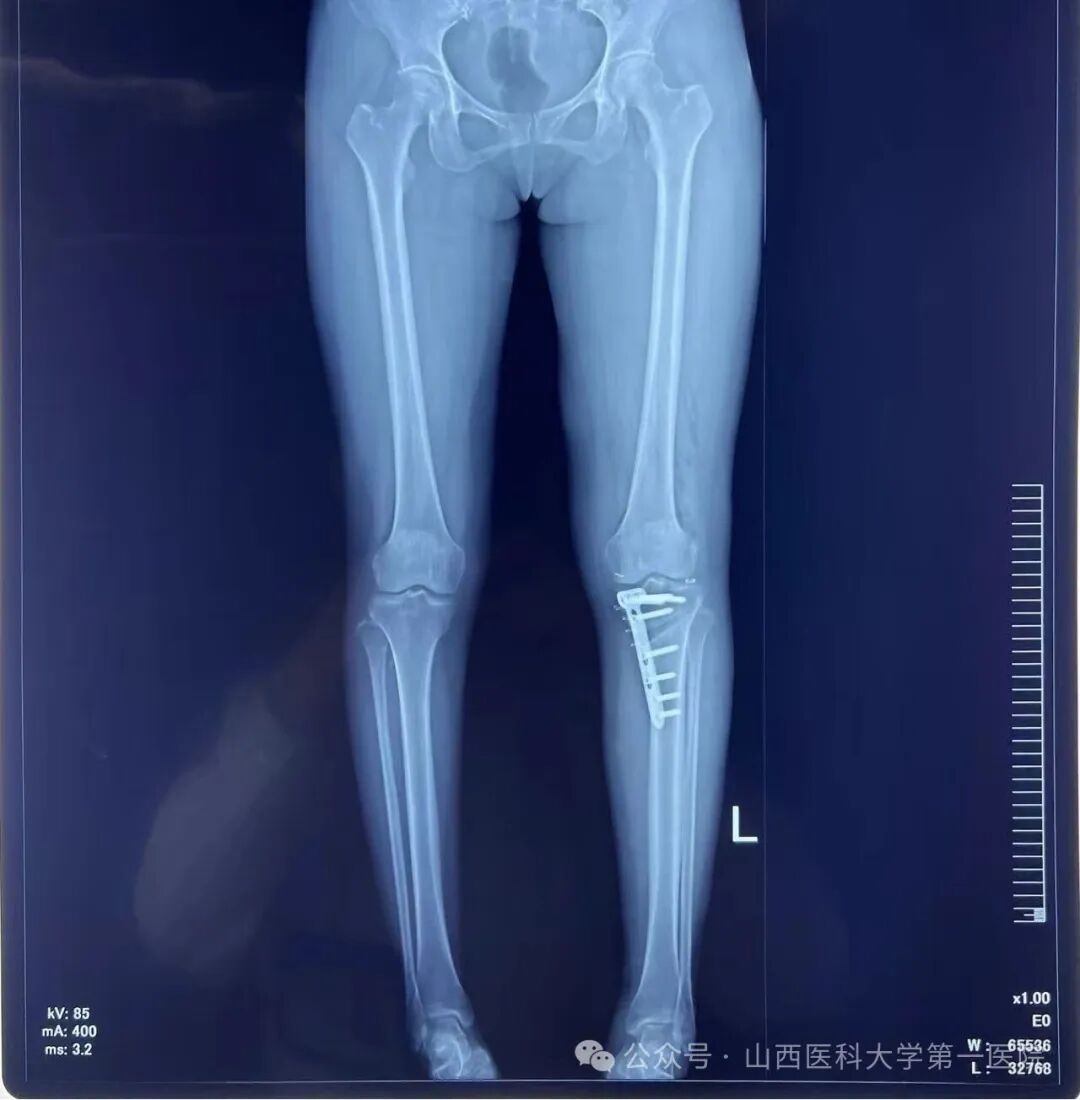

术后左下肢力线明显矫正

此次手术患者的膝关节核磁显示半月板有明显的撕裂,因此单纯行HTO无法解决半月板损伤的问题。骨科主任杨自权作为山西省运动医学的领军人物,运用关节镜为患者解决半月板损伤的问题,同时在AI设计的3D-PSI的辅助下实施精确地截骨矫正下肢机械轴力线,从而达到令人满意的手术效果。